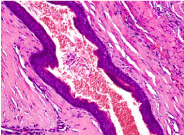

Figure 3. Stratified epithelium with parakeratinization.